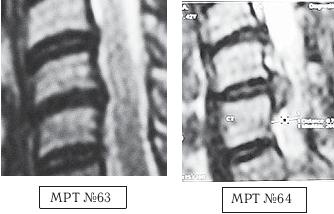

На МРТ № 62 от 07.04.2003 того же пациента наблюдается грыжа межпозвонкового диска LIV-LV с сдавлением дурального мешка, абсолютным стенозом на уровне данного сегмента и увеличением протрузии в сегменте LV—SI. Вот ещё один пример. Произошло это несчастье по причине того, что в течение двух месяцев данной пациентке в одном из специализированных центров врач «вертебролог-вертеброневролог» проводил вытяжения шейного отдела позвоночника с применением петли Глиссона на наклонной плоскости под силой тяжести собственного веса самой пациентки. На жалобы пациентки о том, что после нескольких сеансов самочувствие ухудшилось и усилились боли, врач объяснял, что «это нормально, просто позвонки растягиваются, и межпозвонковые диски становятся на место, поэтому происходит обострение». Но после того как данная пациентка во время очередного сеанса потеряла сознание, ей сделали контрольное МРТ шейного отдела позвоночника (МРТ № 64, была обнаружена секвестрированная грыжа межпозвонкового диска), а затем в срочном порядке направили в нейрохирургию. Этот случай свидетельствует о некомпетентности этого врача «вертебролога-вертеброневролога» и ещё раз подчёркивает, насколько важно в нашем обществе самому пациенту владеть информацией о своём позвоночнике, о процессах, в нём происходящих, и о способах лечения. ![]() На МРТ № 63 наблюдается фрагмент шейного отдела позвоночника. На данном уровне отчётливо видно исправление лордоза, стеноз спинномозгового канала, небольшие протрузии практически компенсированные спондилёзом в сегментах СV-СVI, СVI—СVII, гипертрофия задней продольной связки на данном уровне. На МРТ № 64 наблюдается фрагмент шейного отдела позвоночника той же пациентки через два месяца. На снимке видно, что к имевшимся (на МРТ № 63) проблемам добавилась ещё и грыжа в сегменте СV-СVI, и секвестрированная грыжа межпозвонкового диска в сегменте СVI-СVII.. Следующий пример также довольно типичный, как пациент, из-за недостатка знаний, усугубил состояние своего здоровья. Данный пациент периодически испытывал кратковременные боли в поясничном отделе позвоночника. По его словам, они, как правило, возникали «после длительного сидения, в момент вставания» (стартовые боли) и быстро проходили. Пациент обратился в районную больницу по этому поводу. Сделали МРТ (№ 65). Врачи не обнаружили на снимке существенных патологий, поэтому выписали пациенту лекарства и посоветовали меньше сидеть и больше двигаться. Однако, так как эти боли продолжали доставлять пациенту некоторые неудобства, он решил самостоятельно от них избавиться, причём как обещают в рекламе «раз и навсегда». Для этого он, по его словам, «выбрал для себя наиболее удобный способ». То есть, приобрёл широко рекламируемое устройство для вытяжения позвоночника в домашних условиях. На протяжении нескольких месяцев он добросовестно выполнял предписания из инструкции, прилагавшейся к этому устройству. Как это обычно бывает, вначале действительно стало немного легче, но этот эффект длился недолго. Внезапно появились тянущие боли в ноге. Пациент вновь вынужден был обратиться за помощью в больницу, но дома всё равно продолжал вытяжения позвоночника. А после того как боли усилились настолько, что лекарства уже не помогали, ему повторно сделали МРТ (МРТ № 66). Естественно, ознакомившись с результатом обследования, врачи направили его в нейрохирургию. Вот к каким последствиям приводит отсутствие элементарных знаний и слепая вера во «всесильную» рекламу. Если бы данный пациент знал заранее, к чему может привести вытяжение позвоночника при дегенеративно-дистрофических процессах в позвоночнике, то уж точно не стал бы так рисковать своим здоровьем. ![]() На МРТ № 65 наблюдается нормальный физиологический лордоз, снижение высоты межпозвонкового диска в сегменте LV—SI, вследствие развития в нём дегенеративно-дистрофического процесса (остеохондроза). На МРТ № 66 наблюдается сглаженность физиологического лордоза, грыжа межпозвонкового диска в сегменте LV—SI. Ещё один показательный пример о том, как молодая девятнадцатилетняя девушка попала к «чудо-новатору» по методам вытяжения позвоночника. Началась данная история с того, что у молодой студентки, вследствие длительной работы на компьютере, стали появляться боли в мышцах шеи и плеч. Она обратилась к врачу. Этот «специалист» после осмотра поставил ей предварительный диагноз — «смещение диска» и направил на МРТ. Заметьте, на первый взгляд врач действовал правильно, направив пациента на МРТ уточнить диагноз. Но как потом оказалось, для него это являлось всего лишь формальностью, а не установлением истинной причины происхождения болей и тем более не заботой о выборе щадящих методов лечения. Впрочем, судите сами. После результатов обследования, в описании которого была указана только протрузия в сегменте CVI-CVII размером 1,4 мм центральной локализации, данный врач объяснил, что «это и есть смещение диска, который давит ей на нерв» и предложил его вправить, на что девушка, по своей наивности и из-за отсутствия элементарных знаний о развитии патологии в позвоночнике, согласилась. Более того, на её беду (в прямом смысле слова) этот врач оказался новатором-изобретателем. По его словам, он «совершил настоящую революцию в вертебрологии» (сам он травматолог), «изобрёл чудо-устройство, с помощью которого можно навсегда избавить пациента от остеохондроза». Я не утрирую, это действительно слова данного «специалиста». Он стал рассказывать девушке, что «изобретение» настолько эффективное, что к нему даже японцы приезжали с просьбой продать им это «чудо», но не продал (не по причине патриотизма), просто потому, что японцы хотели его обмануть и предложили слишком мало денег, «всего два миллиона евро». В данном случае вы сами понимаете, что ни о какой порядочности и врачебной этике такого «специалиста» говорить не приходится, если в голове вместо знаний науки вертебрологии только подсчёт количества нулей. ![]() На МРТ № 67 от 17.09.2009 наблюдается шейный отдел позвоночника с признаками формирования протрузий в сегментах CV—CVI, CVI—CVII. Физиологический лордоз сохранён, признаков нарушения проводимости ликворных путей не наблюдается. На МРТ № 68 от 12.10.2009 у той же пациентки наблюдается значительное прогрессирование дегенеративно-дистрофического процесса в шейном отделе позвоночника с осложнениями в виде грыж межпозвонковых дисков CIV-CV, CV-CVI, CV—CVII, сглаживание физиологического лордоза с нарушением ликвородинамики. В действительности же этим «чудом» оказался всего лишь раздвижной стол с изменяемым углом наклона для растяжения позвоночника. Со слов пациентки, её «положили на этот раздвижной стол, к нижней половине стола привязали ноги и таз в районе талии, а к верхней половине привязали голову под челюсть и затылок (очевидно петлёй Глиссона) и начали крутить какую-то ручку, стол стал раздвигаться и наклоняться вниз». После того как вследствие растяжения шейного отдела позвоночника у данной пациентки появились сильные боли, врач сказал «терпеть» и оставил её в такой «растяжке» на десять минут. После чего пояснил, что таких сеансов «вправления выпавшего диска» ей надо пройти как минимум десять и тогда всё будет хорошо. До десяти сеансов пациентка не дотянула, так как «хорошо» ей уже стало после шестого сеанса, начались синкопические состояния (состояние перед обмороком), боль и онемение в правой руке, головокружение и нарушение координации при ходьбе. |